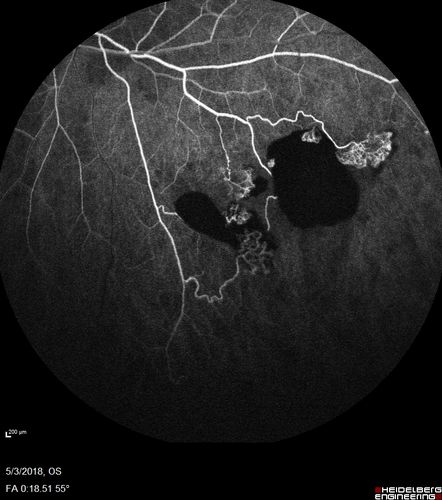

Coats' Disease -51 year old asymptomatic male

20/20 vision - had laser to non-perfusion because of proliferation.